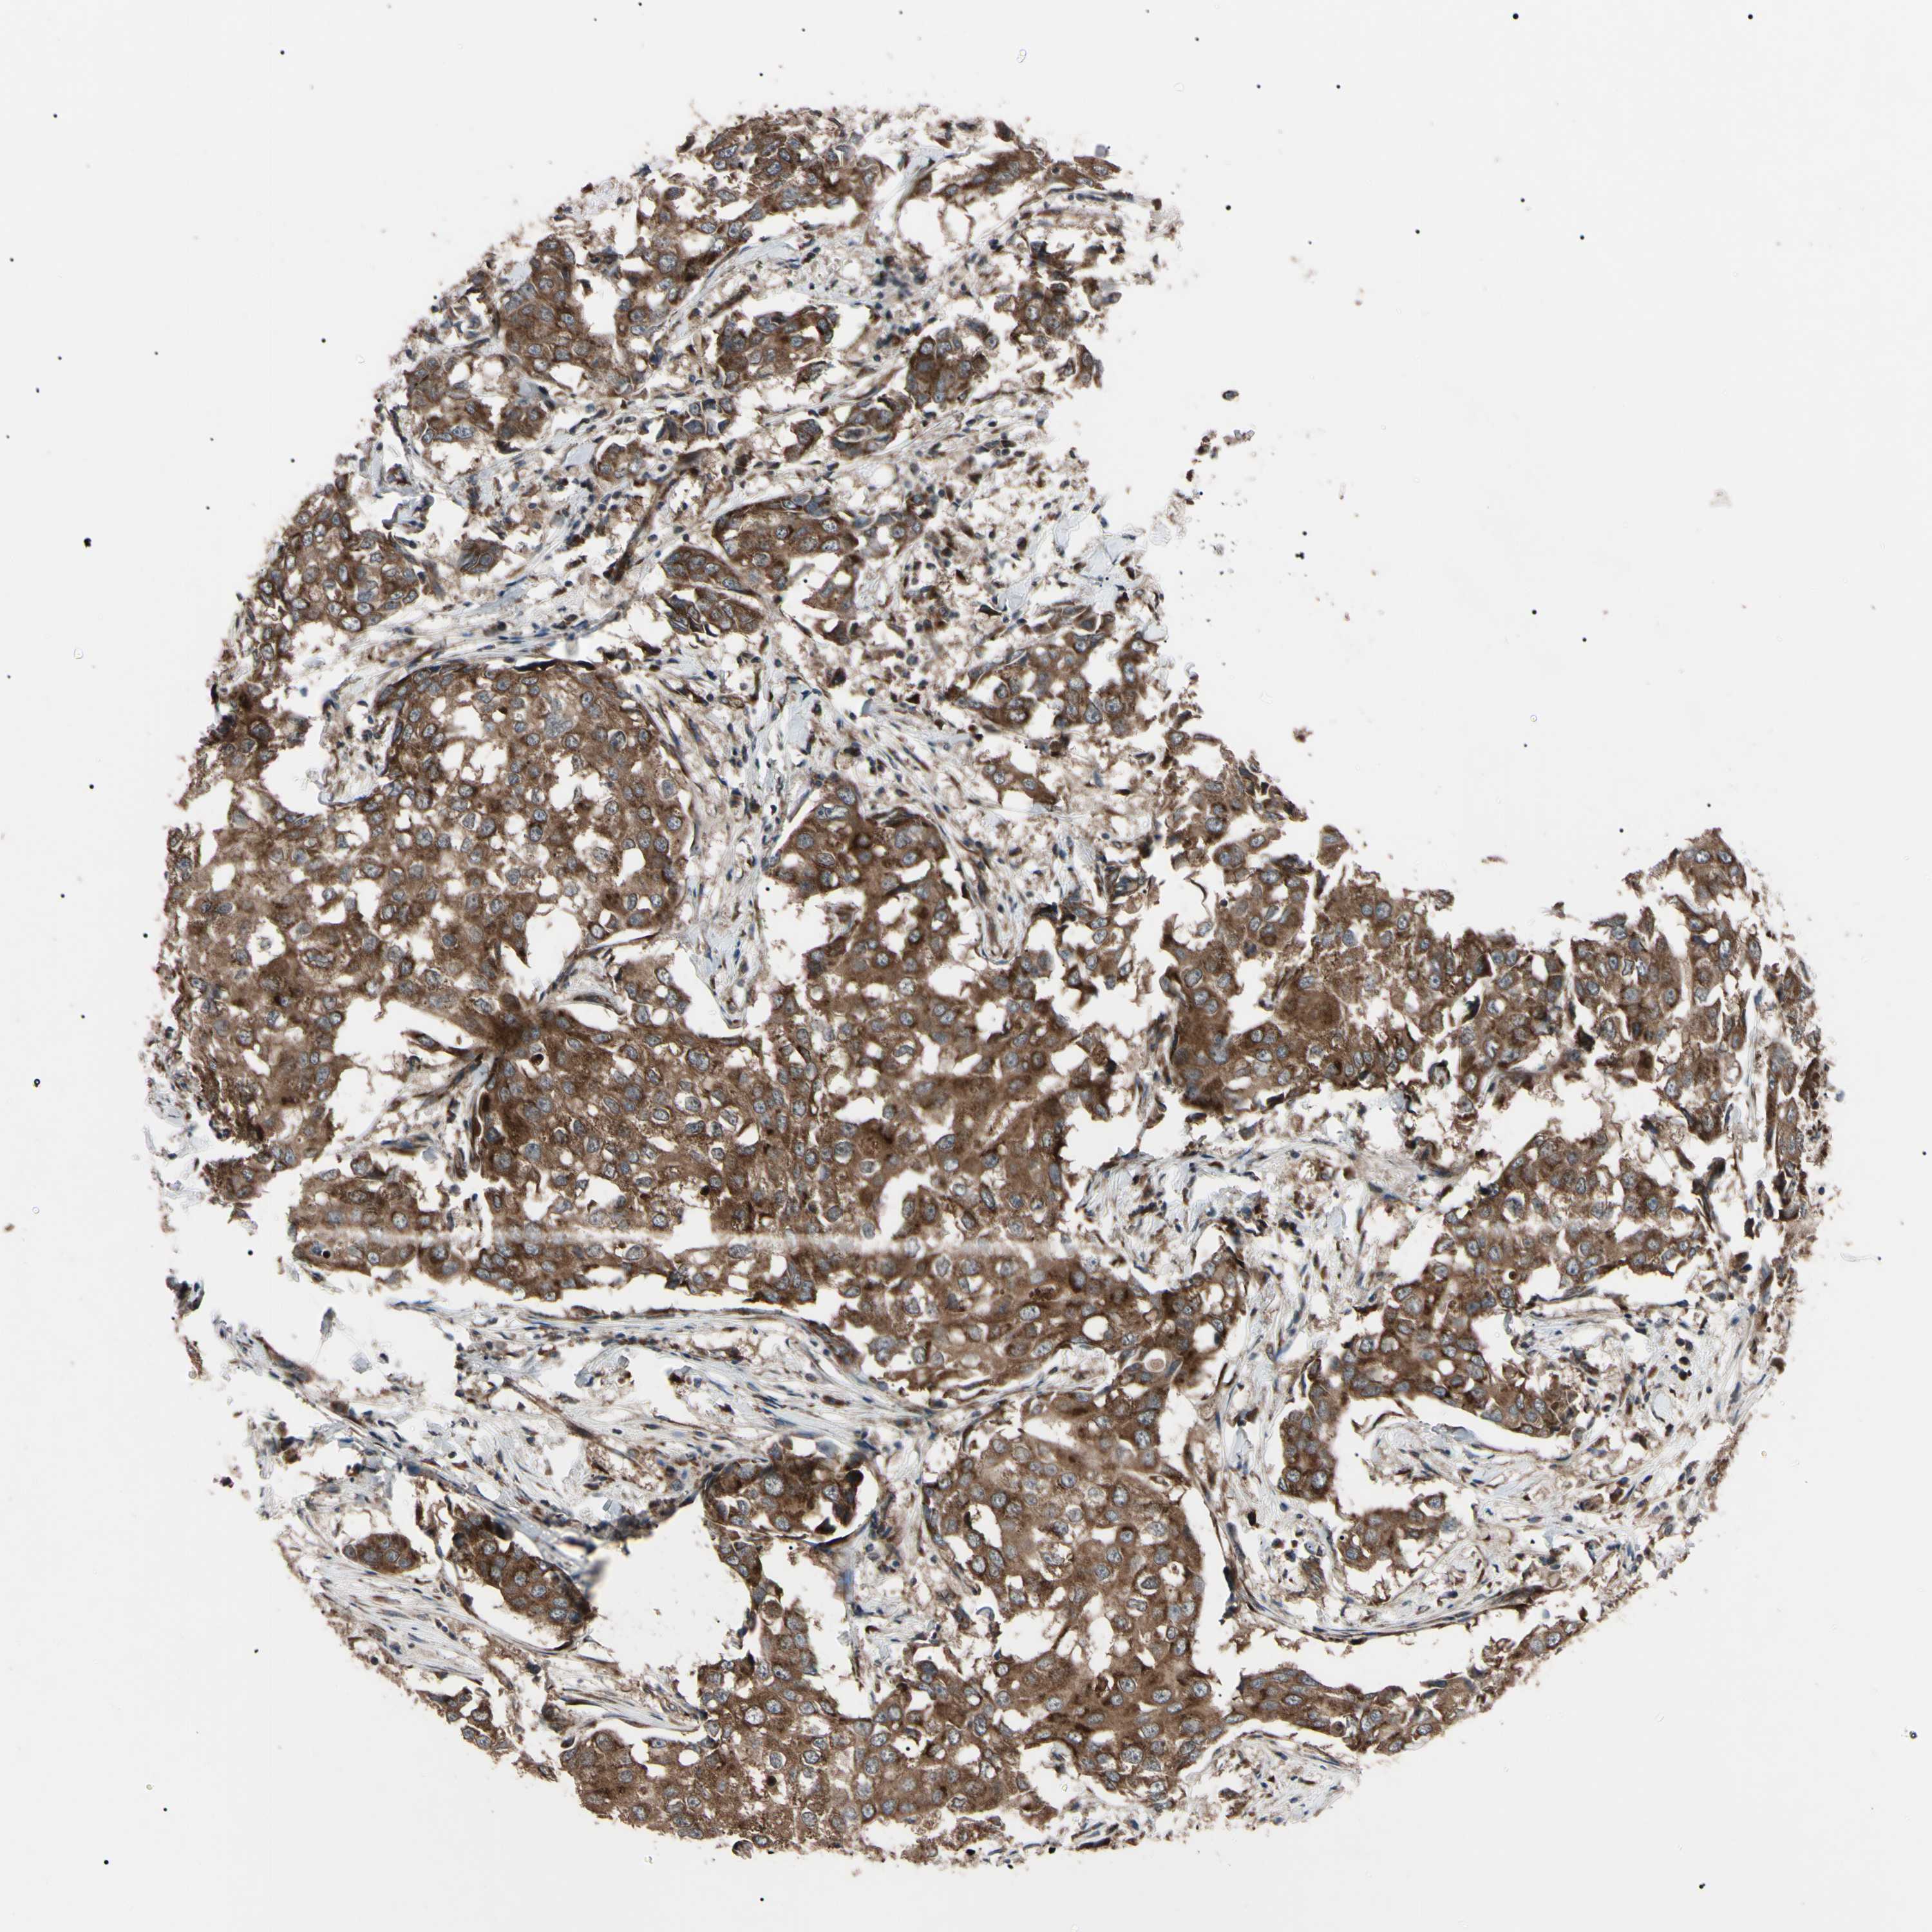

BRCA TCGA BRCA VALIDATION PROTEIN EXPRESSION